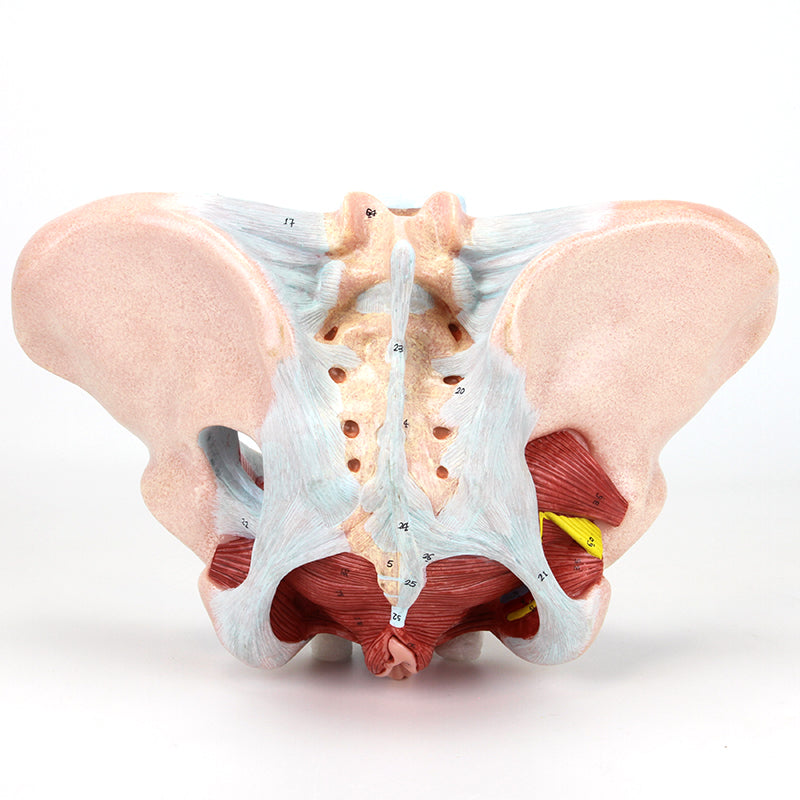

女性骨盤モデル(靭帯、血管、神経、骨盤底筋付き)

この実物大の女性骨盤は、仙腸靭帯、骨盤底筋、神経網および仙骨血管とともに、骨盤の外性器および内性器の構造を手描きで示しています。筋肉や靭帯の筋理を細かく描写しており、このモデルに高品質で詳細な印象を与えています。このモデルは女性の骨格系を理解するための優れた学習教材であり、すべての学生に適しています。さらに、神経痛、筋肉の緊張、靭帯の損傷を患者に説明する際にも役立ちます。拡張現実を用いたインタラクティブな三次元解剖モデルと併用することで、学習を促進し支援する優れたツールとなります。このプラットフォームは、学生が個々の器官の構造を比較・対照しながら解剖モデルの比較分析に取り組むことを可能にします。また、この取り組みは継続教育の場を提供し、すべての学生が解剖学、生理学および病理生理学の知識を深める機会を提供します。

女性骨盤モデル(靭帯、血管、神経、骨盤底筋付き)

この実物大の女性骨盤は、仙腸靭帯、骨盤底筋、神経網および仙骨血管とともに、骨盤の外性器および内性器の構造を手描きで示しています。筋肉や靭帯の筋理を細かく描写しており、このモデルに高品質で詳細な印象を与えています。このモデルは女性の骨格系を理解するための優れた学習教材であり、すべての学生に適しています。さらに、神経痛、筋肉の緊張、靭帯の損傷を患者に説明する際にも役立ちます。拡張現実を用いたインタラクティブな三次元解剖モデルと併用することで、学習を促進し支援する優れたツールとなります。このプラットフォームは、学生が個々の器官の構造を比較・対照しながら解剖モデルの比較分析に取り組むことを可能にします。また、この取り組みは継続教育の場を提供し、すべての学生が解剖学、生理学および病理生理学の知識を深める機会を提供します。